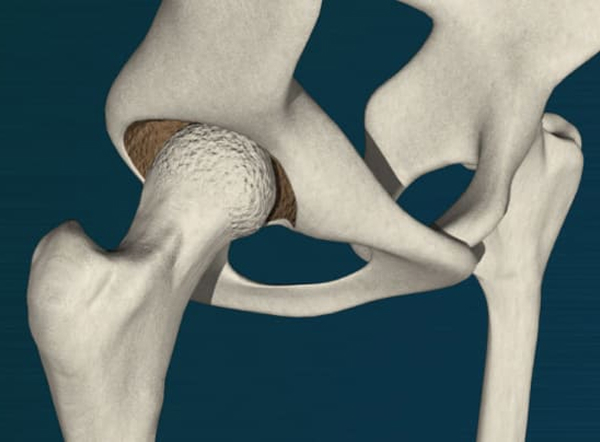

股関節の場合

手術は股関節のやや後方、または外側、あるいは前方の皮膚を切開して行います。

• ロボティックアームを用いて骨盤(臼蓋)の表面を整えます。

• ロボティックアームを用いてインプラントを設置します。